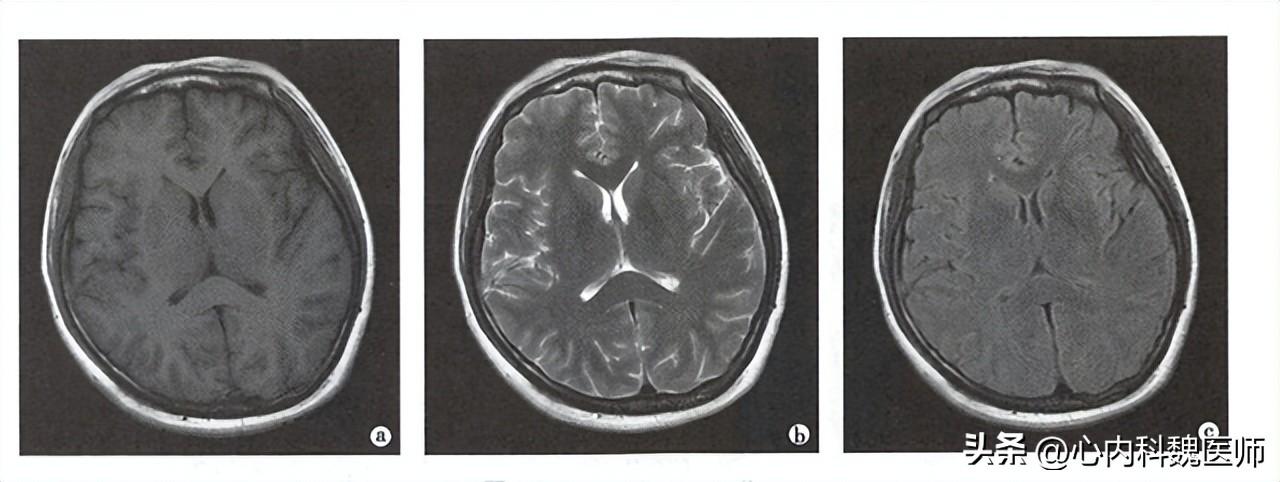

一、磁共振是什么,主要运用于什么

磁共振又叫核磁共振英文简称MRI,主要是利用人体处于强大的磁场内所产生的氢质子,在特定射频(RF)脉冲的作用下产生的磁共振的现象。

磁共振的成像过程较X线、CT等更为复杂,他的成像原理主要是下面这几个步骤:

首先是当我们的人体进入到一个强大的磁场里面,使本来有自己运动轨迹的氢质子改变运动方向。

然后再给一个特定的射频让原来被改变的氢质子运动方向再次改变其中一只和原来运动的方向相同,另外一直相反。

最后,结束射频这个力量,氢质子运动方向恢复的时间,经过计算机分析得到的黑白灰三个不同程度的显影,就是磁共振结果我们看到的图像,我们可以根据颜色的深浅,来判断疾病的发展程度。

其次磁共振可以对血液的特殊显影,迅速在脑部扫描后很快显影效果,如:脑出血、脑梗死等,对位置判断和出血、梗死范围都可以迅速定位。

磁共振可以根据血液本来的流动效应,甚至不用造影剂,根据氢质子的运动方向可以更好的标记血液流动,就可以加强对比效果就可以迅速显影血管内的改变,来尽快明确血管内疾病。